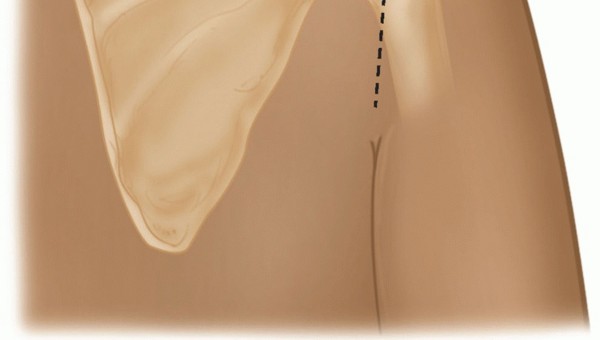

A longitudinal incision in the posterior axillary fold is made beginning at a point 2 cm medial to the posterolateral corner of the acromion and extending distally, following the posterior axillary line (TECH FIG 3).

- TECH FIG 3 • The posterior longitudinal incision begins about 2 cm medial to the posterolateral corner of the acromion and extends into the axillary crease.